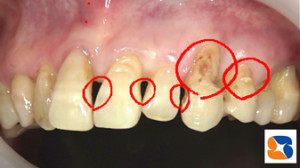

歯と歯の間や際にできた虫歯

コラム「歯と歯の間や際にできた虫歯」の画像